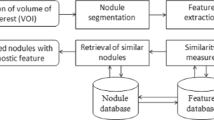

Similarity measurement of lung nodules is a critical component in content-based image retrieval (CBIR), which can be useful in differentiating between benign and malignant lung nodules on computer tomography (CT). This paper proposes a new two-step CBIR scheme (TSCBIR) for computer-aided diagnosis of lung nodules. Two similarity metrics, semantic relevance and visual similarity, are introduced to measure the similarity of different nodules. The first step is to search for K most similar reference ROIs for each queried ROI with the semantic relevance metric. The second step is to weight each retrieved ROI based on its visual similarity to the queried ROI. The probability is computed to predict the likelihood of the queried ROI depicting a malignant lesion. In order to verify the feasibility of the proposed algorithm, a lung nodule dataset including 366 nodule regions of interest (ROIs) is assembled from LIDC-IDRI lung images on CT scans. Three groups of texture features are implemented to represent a nodule ROI. Our experimental results on the assembled lung nodule dataset show good performance improvement over existing popular classifiers.